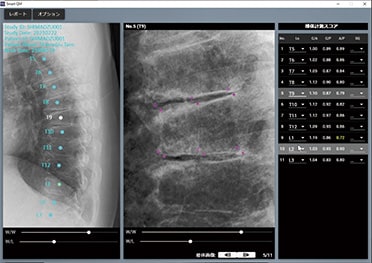

Vertebral fracture examinations by the QM method can be performed easily by specifying the measurement locations automatically.

*This option is only available in the Japanese market.

Through that collaboration, we developed vertebral body measurement software for quickly and easily diagnosing osteoporosis using artificial intelligence (AI). We are also engaged in joint research for using mass spectrometry to investigate vitamin D measurements and engaged in creating and validating systems initiated during health checkups for prevention and early detection of osteoporosis based on routine health data and clinical data.